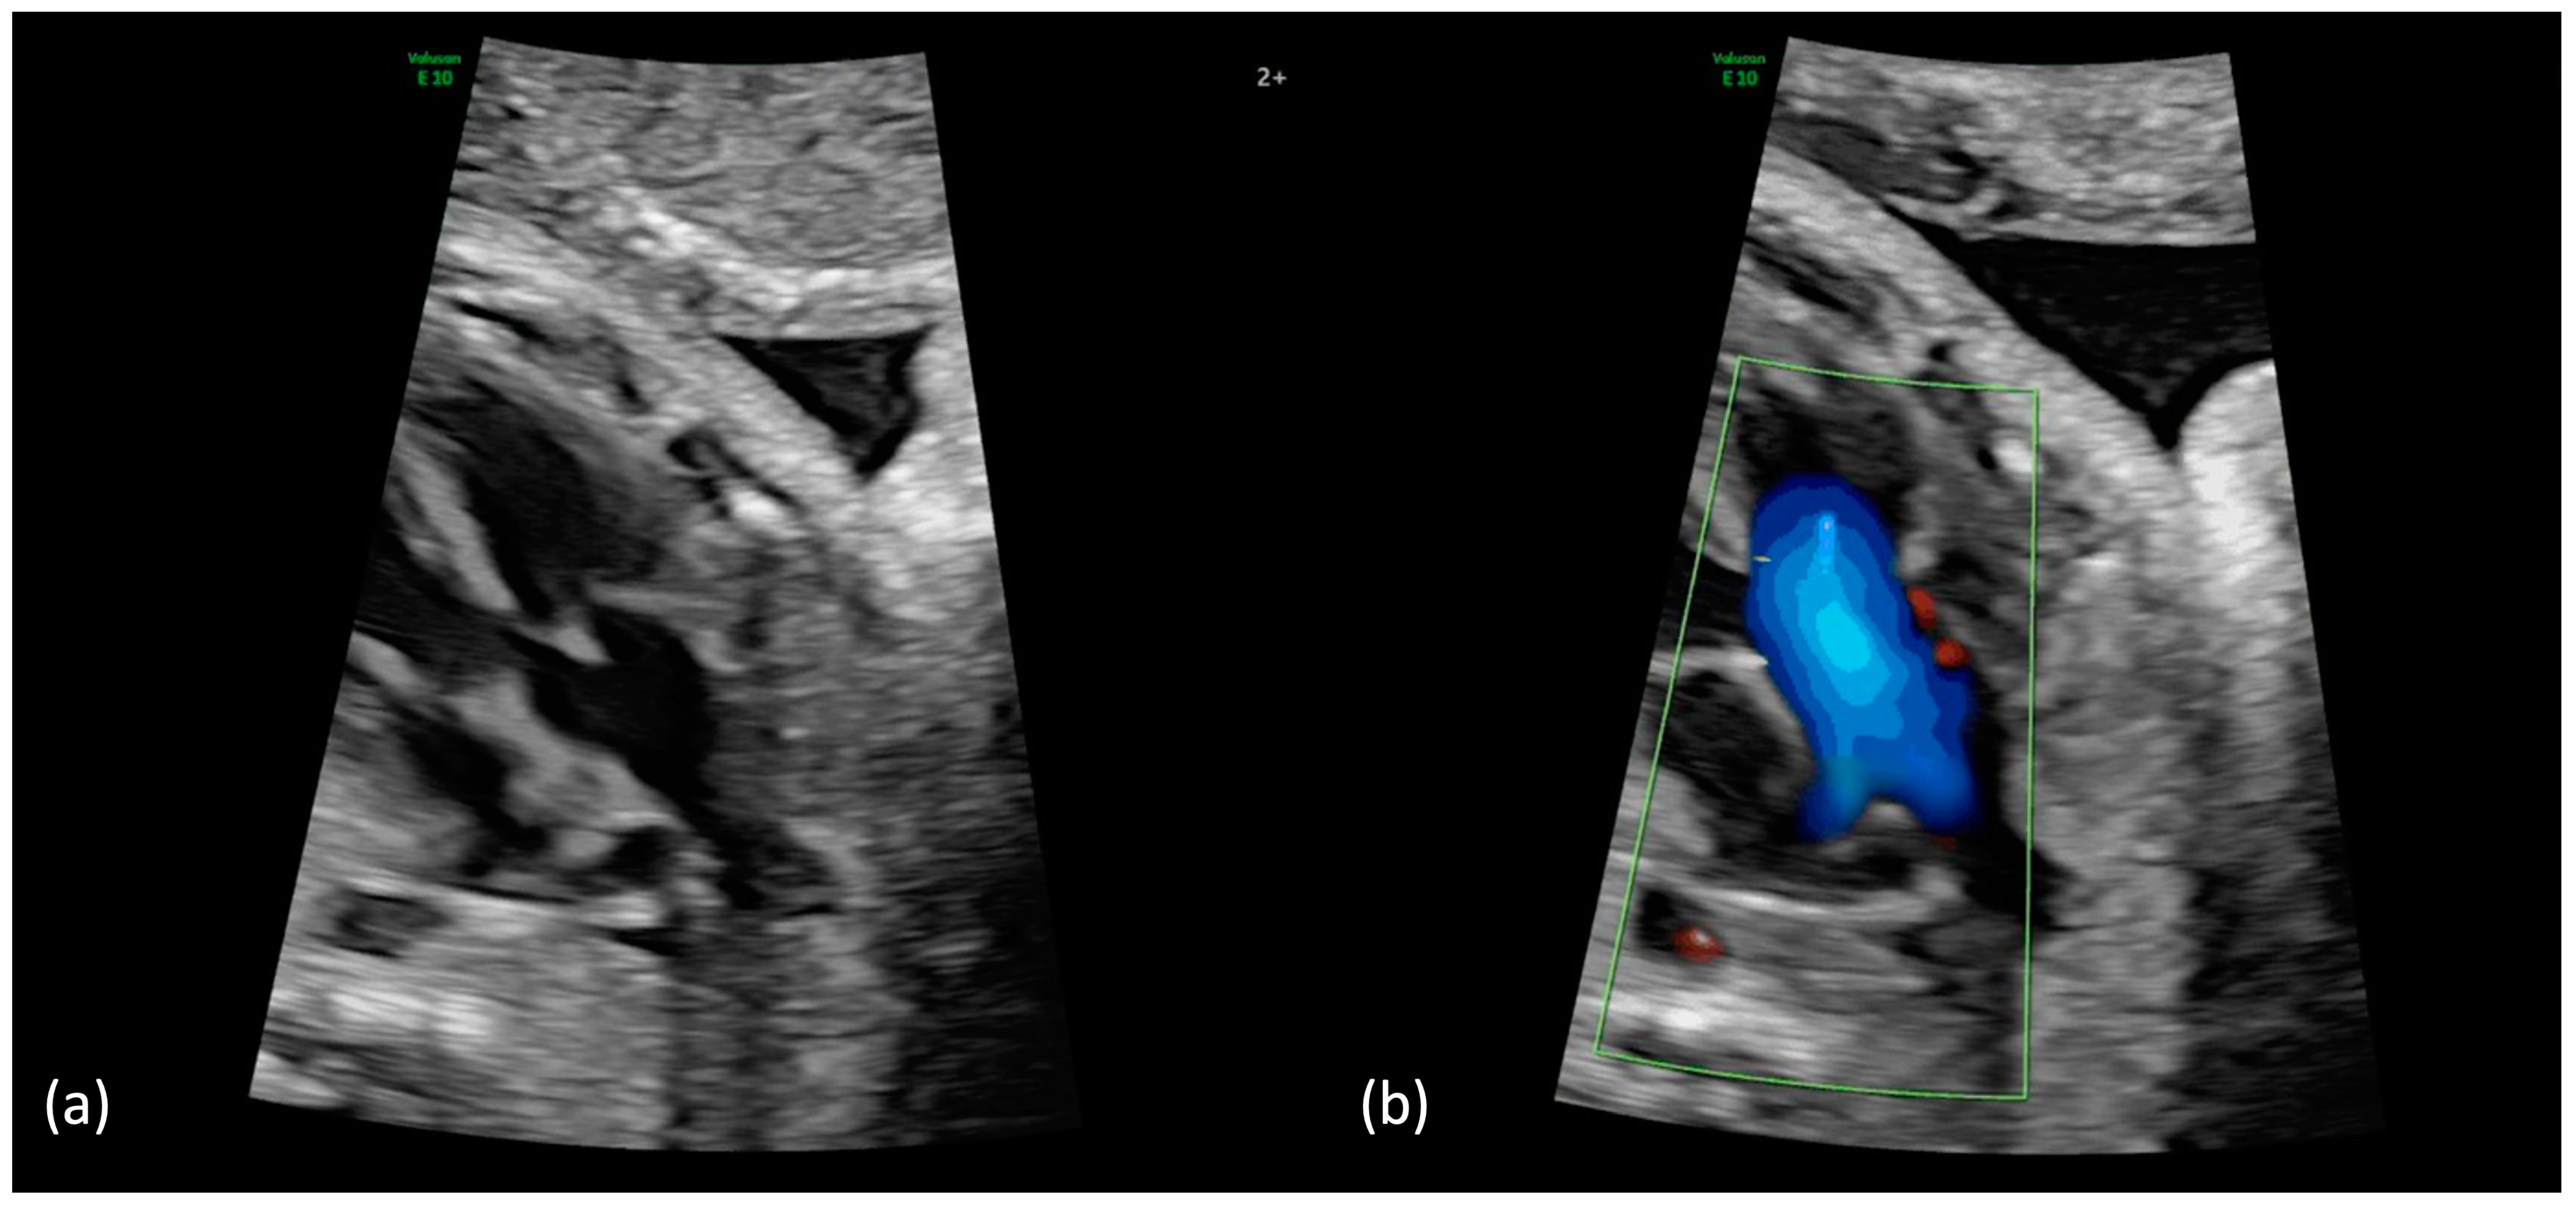

Figure 1.

(a,b): Truncus arteriosus type 1 at 31 + 4 weeks. (a) Perimembranous outlet VSD as interventricular communication with the broad common arterial trunk in the overriding position. (b) In the color Doppler mode, the filling of the common arterial trunk from both ventricles and the posterior branch of one pulmonary artery can be seen (aortic dominance); aliasing or a high variance, which indicates a stenosis of the truncal valve, is not present.